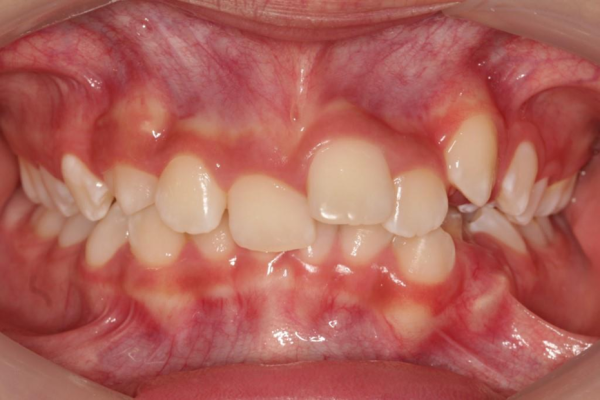

Caso de apiñamiento y sobremordida

Paciente pediátrico, masculino de 9 años de edad, acude acompañado de sus padres debido a la mala alineación de los dientes, y encías inflamadas (gingivitis). Buscan mejorar tanto la estética como la salud bucal desde una etapa temprana.

El paciente en su consulta de diagnóstico

Durante la valoración clínica se identificaron los siguientes hallazgos:

- Apiñamiento dental moderado en ambas arcadas

- Falta espacio para la erupción correcta de caninos superiores

- Sobremordida aumentada

- Encías inflamadas con enrojecimiento generalizado (gingivitis)

- Dentición mixta (presencia de dientes temporales y permanentes)